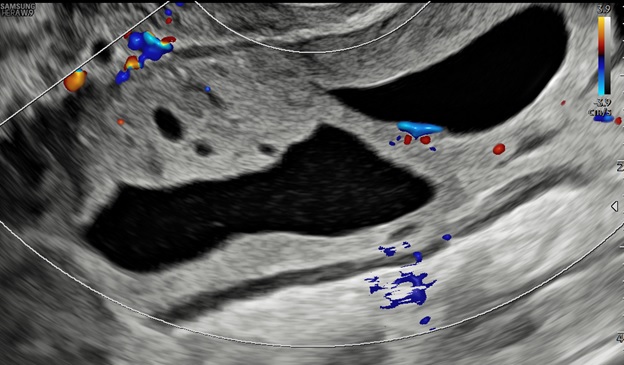

Hình 2: Mặt cắt dọc và ngang qua ngã âm đạo thấy khối u có phản âm hỗn hợp, bên trong có nhiều mảng phản âm dày, di động khi di chuyển đầu dò, giúp hướng đến bản chất xuất huyết.

Hình 5: Siêu âm ngã âm đạo cho thấy thành u có tăng sinh mạch máu độ 2